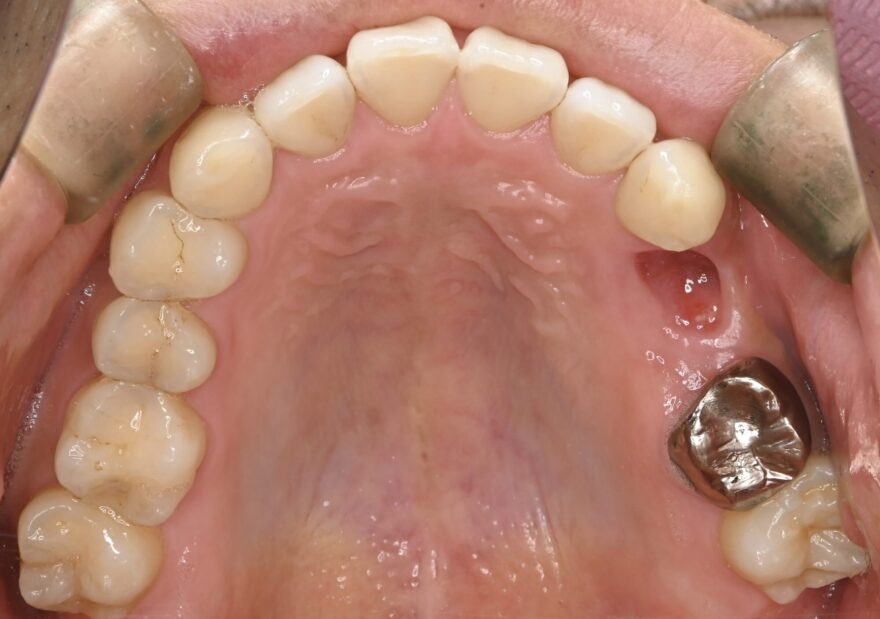

治療前の口腔内写真

治療前のレントゲン写真

両サイドに2本のインプラントを埋め込み、3本の上部構造を支えるインプラントブリッジを患者様に提案しました。

埋め込むインプラントを3本ではなく2本にすることで、オペ後の腫れと痛みを少なく、治療費も少なくできます。